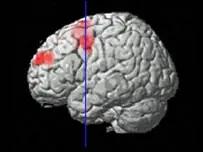

Escáneres cerebrales realizados a sujetos participantes en un estudio, y que aseguraban sentir odio, mostraban una actividad neurológica muy similar al sentimiento contrario, según aseguran los científicos que han llevado a cabo la investigación.

En su estudio, los investigadores enseñaron a 17 personas de ambos sexos las fotografías de varios sujetos, mientras registraban punto por punto la respuesta a esa acción en su cerebro. Entre las imágenes aparecían personas que ellos mismos habían señalado antes como queridas, odiadas o neutrales. Al analizar el resultado del escáner, se detectó un patrón de actividad en varias áreas cerebrales, que los científicos calificaron como "circuito del odio".

Pero siguiendo la línea de ese circuito, los científicos también llegaron a dos zonas conocidas como putamen e ínsula, que se encendían como un árbol de navidad en la pantalla del escáner además cuando las fotografías que veía el sujeto eran de alguien querido. Así que si alguna vez pensaste que estabas totalmente loco por odiar a alguien que antes amabas profundamente o viceversa, no te alteres, es algo perfectamente normal.

El odio comparte estructuras cerebrales que también se activan con el amor.